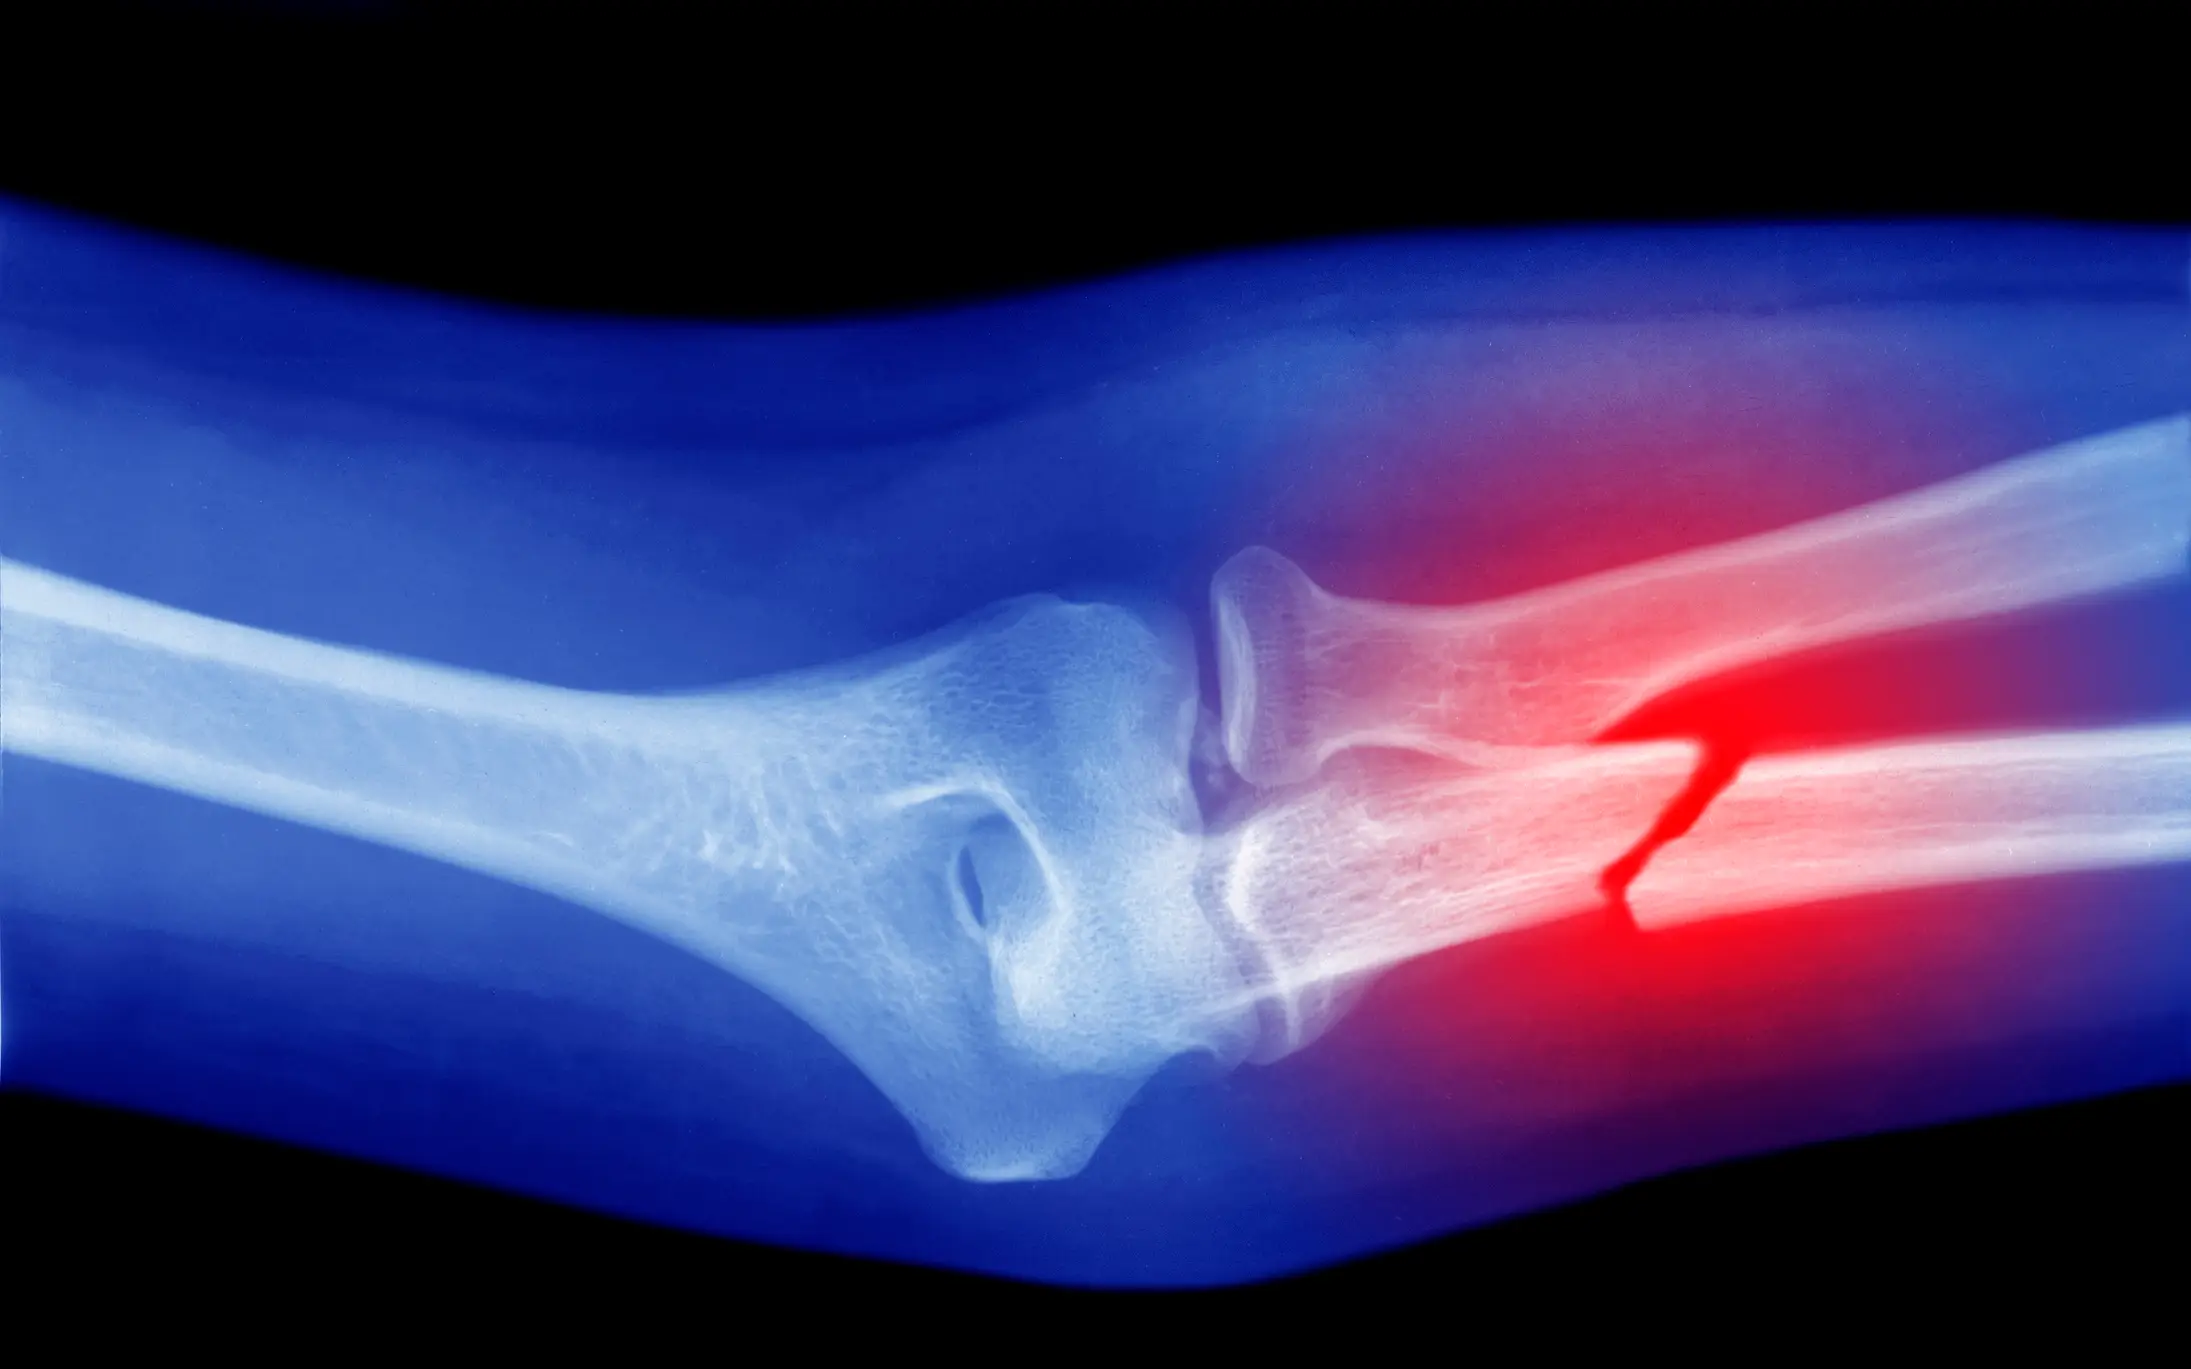

Mayo Clinic describes the condition as something that 'causes bones to become weak and brittle — so brittle that a fall or even mild stresses such as bending over or coughing can cause a break'.

Symptoms of osteoporosis include back pain; loss of height over time; a stooped posture; and bones that break more easily than expected.